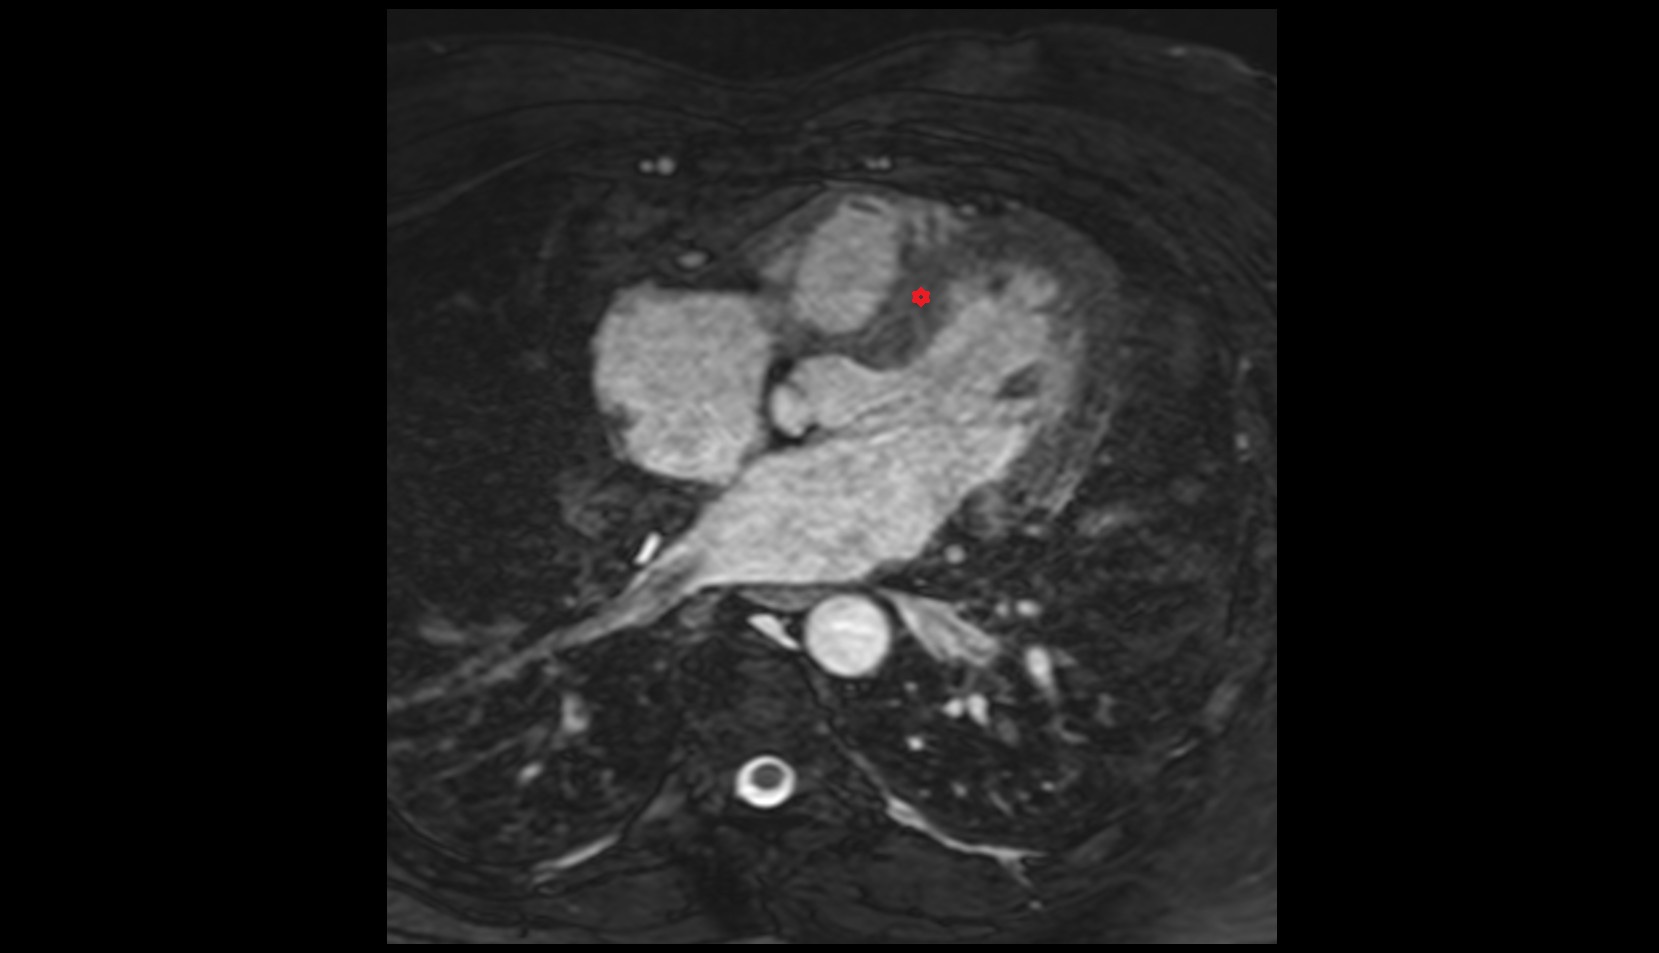

- Pericardium

- Heart

- Left ventricle

- Right atrium

- Left atrium

- Right ventricle

- Pulmonary trunk

- Interventricular Septum

- Ascending aorta